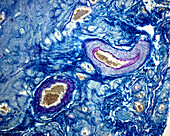

13742427 - Elastic artery, light micrograph

13742425 - Elastic arteries, light micrograph